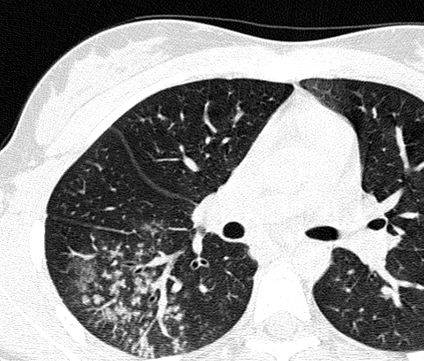

Чтобы человек несведущий смог разобраться в результатах КТ, следует знать о нюансах чтения снимков. Рассмотрим самые актуальные:

- Очаговые образования представляют собой участки белого цвета на черном фоне (на снимке-негативе). В реальности пораженная область, скорее всего, имеет более темный цвет, чем здоровые ткани легкого.

- Если врач заметит на снимке участки кальцинирования или обызвествления (капсул, пропитанных солями кальция) вокруг очага, это может быть признаком доброкачественности образования. Кальцинаты по цвету похожи на кости скелета, видимые на этом снимке. Такие явления часто обнаруживаются после затяжных простудных заболеваний, бронхитов или уже излечененного туберкулеза и представляют собой некий шрам на легких. Пациента с образованием, на котором заметны признаки кальцината, пульмонологи обычно просят раз в полгода делать контрольные снимки.

- В случае, когда образование представляет собой так называемое «облачко» или очаг по типу «матового стекла», требуется более предметное обследование. Внешне оно выглядит как затуманенная область с размытыми границами. В ряде стран пациентам с такими образованиями сразу рекомендуется операция, даже если оно не растет. Уже доказано, что в 80% случаев такие очаги являются предраковым состоянием легких. Альтернатива немедленной операции — постоянное наблюдение с контрольными снимками раз в полгода-год.

Очаговые изменения

Очаговые изменения в лёгких могут быть разного размера. Очаги мелкого диаметра 1-10 мм выявляются при различных диффузных патологиях лёгочной ткани. Очаги с высокой плотностью и довольно чётки краями в основном наблюдаются в интерстиции лёгкого. Различные очаги низкой плотности, напоминающие матовое стекло, с нечёткими контурами возникают при патологических изменениях в респираторных отделах дыхательных органов.

Нужно учитывать, что плотность и размер очагов имеет слабое диагностическое значение. Для постановки диагноза более важным может быть распределение патологических процессов в лёгочной ткани:

- Перилимфатический очаг – часто наблюдается в бронхах, сосудах, в междольковых перегородках и листках плевры. В таком случае видны неровные контуры анатомических структур, при этом перегородочки и стенки бронхов несколько утолщены, как и стенки сосудов. Подобные патологические изменения часто встречаются при туберкулёзе, силикозе, саркоидозе и карциноматозе. При этих патологиях очаги небольшие и не превышают 2-5 мм. Состоят такие очаги из гранулем или метастатических узелочков, они наблюдаются вдоль лимфатических узелков в ткани лёгких и плевре.

- Полиморфный очаг. Такие очаговые образования в ткани лёгких возникают при туберкулёзе. В этом случае КТ позволяет увидеть участки разной плотности и размеров. В некоторых случаях такая картина наблюдается при онкологических патологиях.

- Центрилобулярные очаги. Наблюдаются в артериях и бронхах или в непосредственной близости от них. Они могут быть довольно плотными, хорошо очерченными и однородными. Изменения лёгочной ткани такого типа наблюдаются при пневмониях, эндобронхиальном туберкулёзе и разных видах бронхита, преимущественно бактериального происхождения. Есть и другой тип центрилобулярных очагов, в этом случае лёгочная ткань имеет мелкие уплотнения и похожа на матовое стекло.